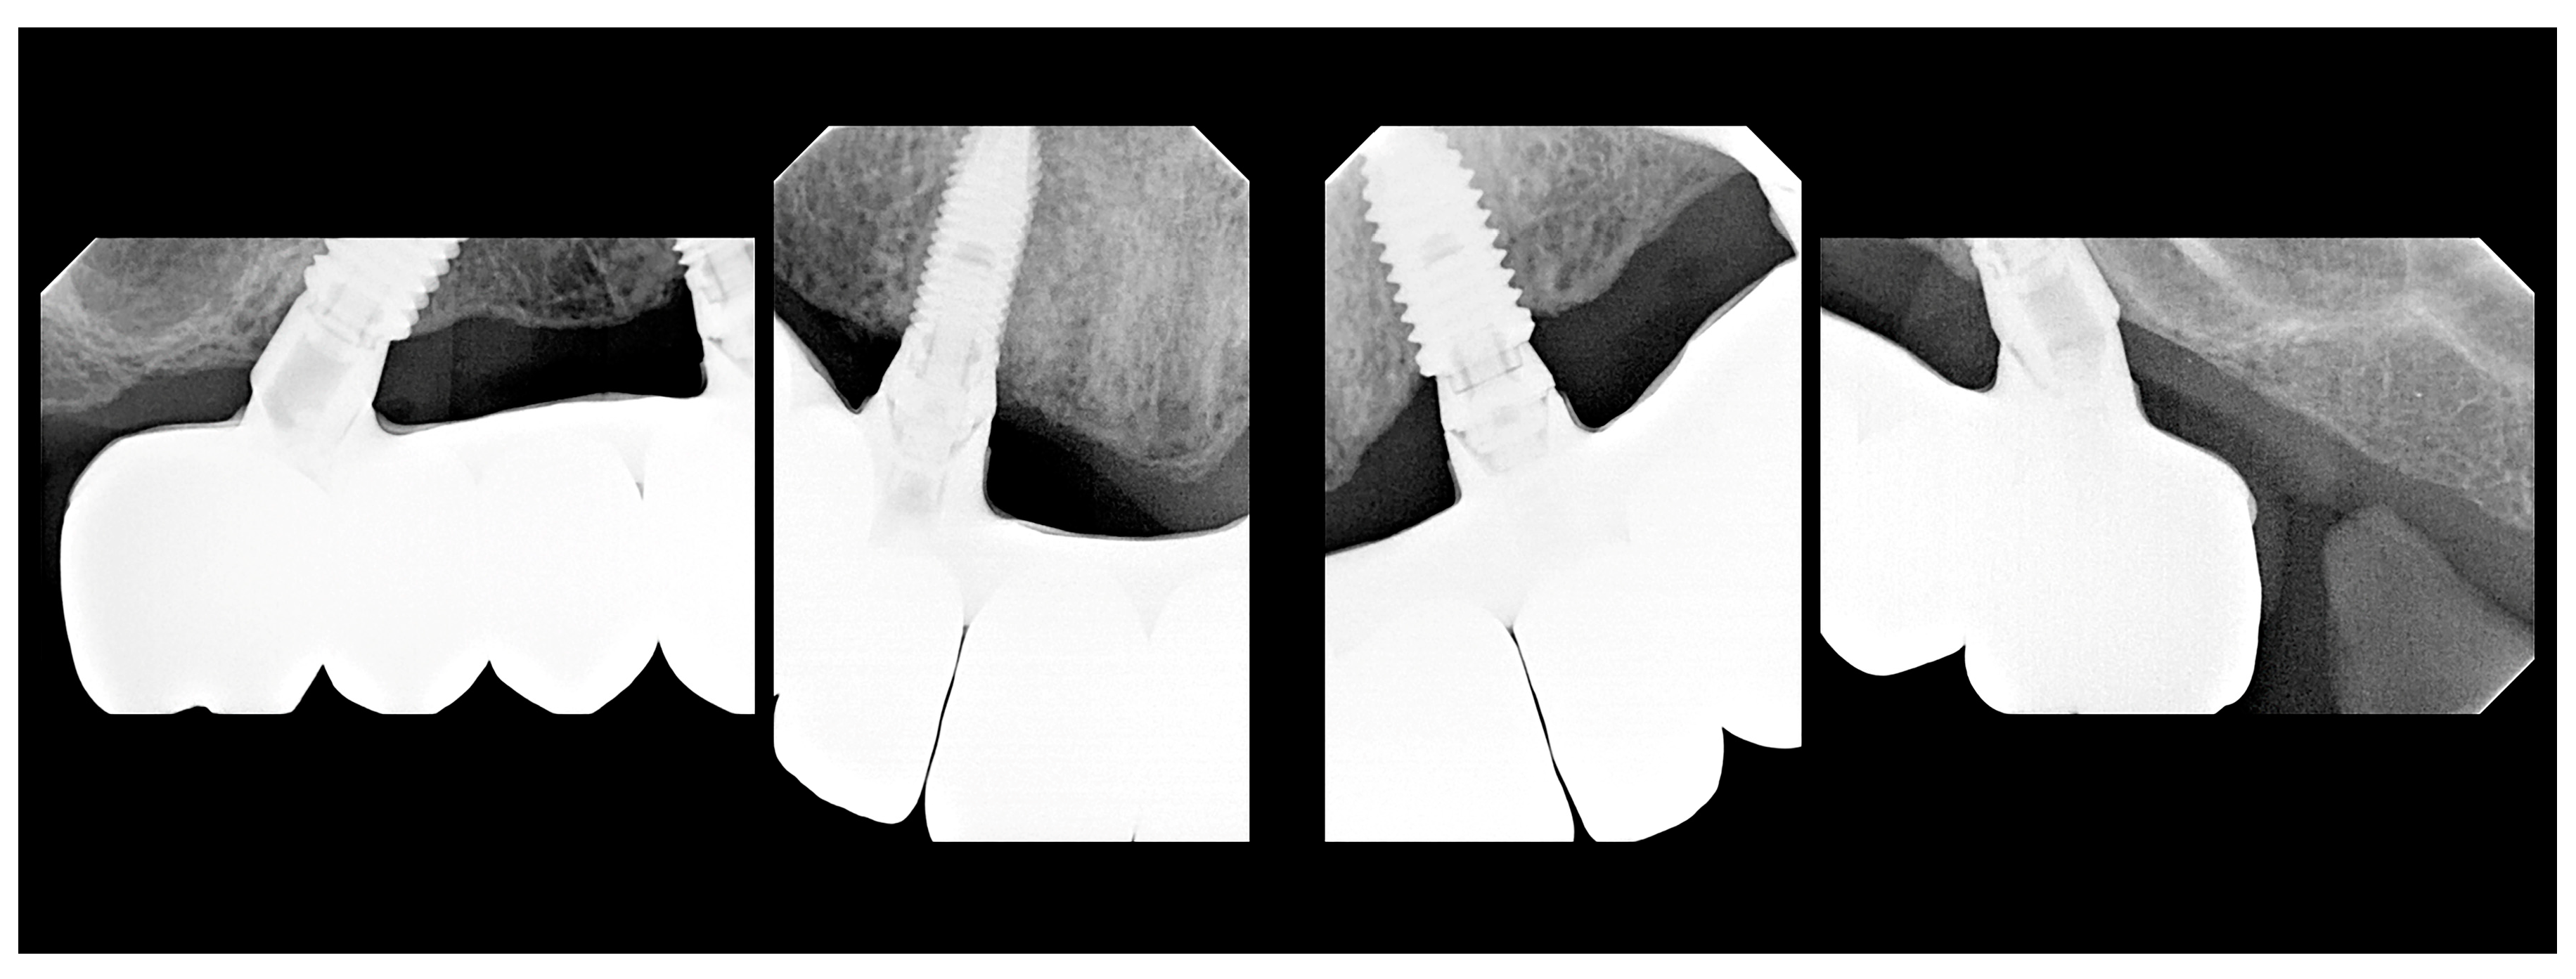

Description of the Technique